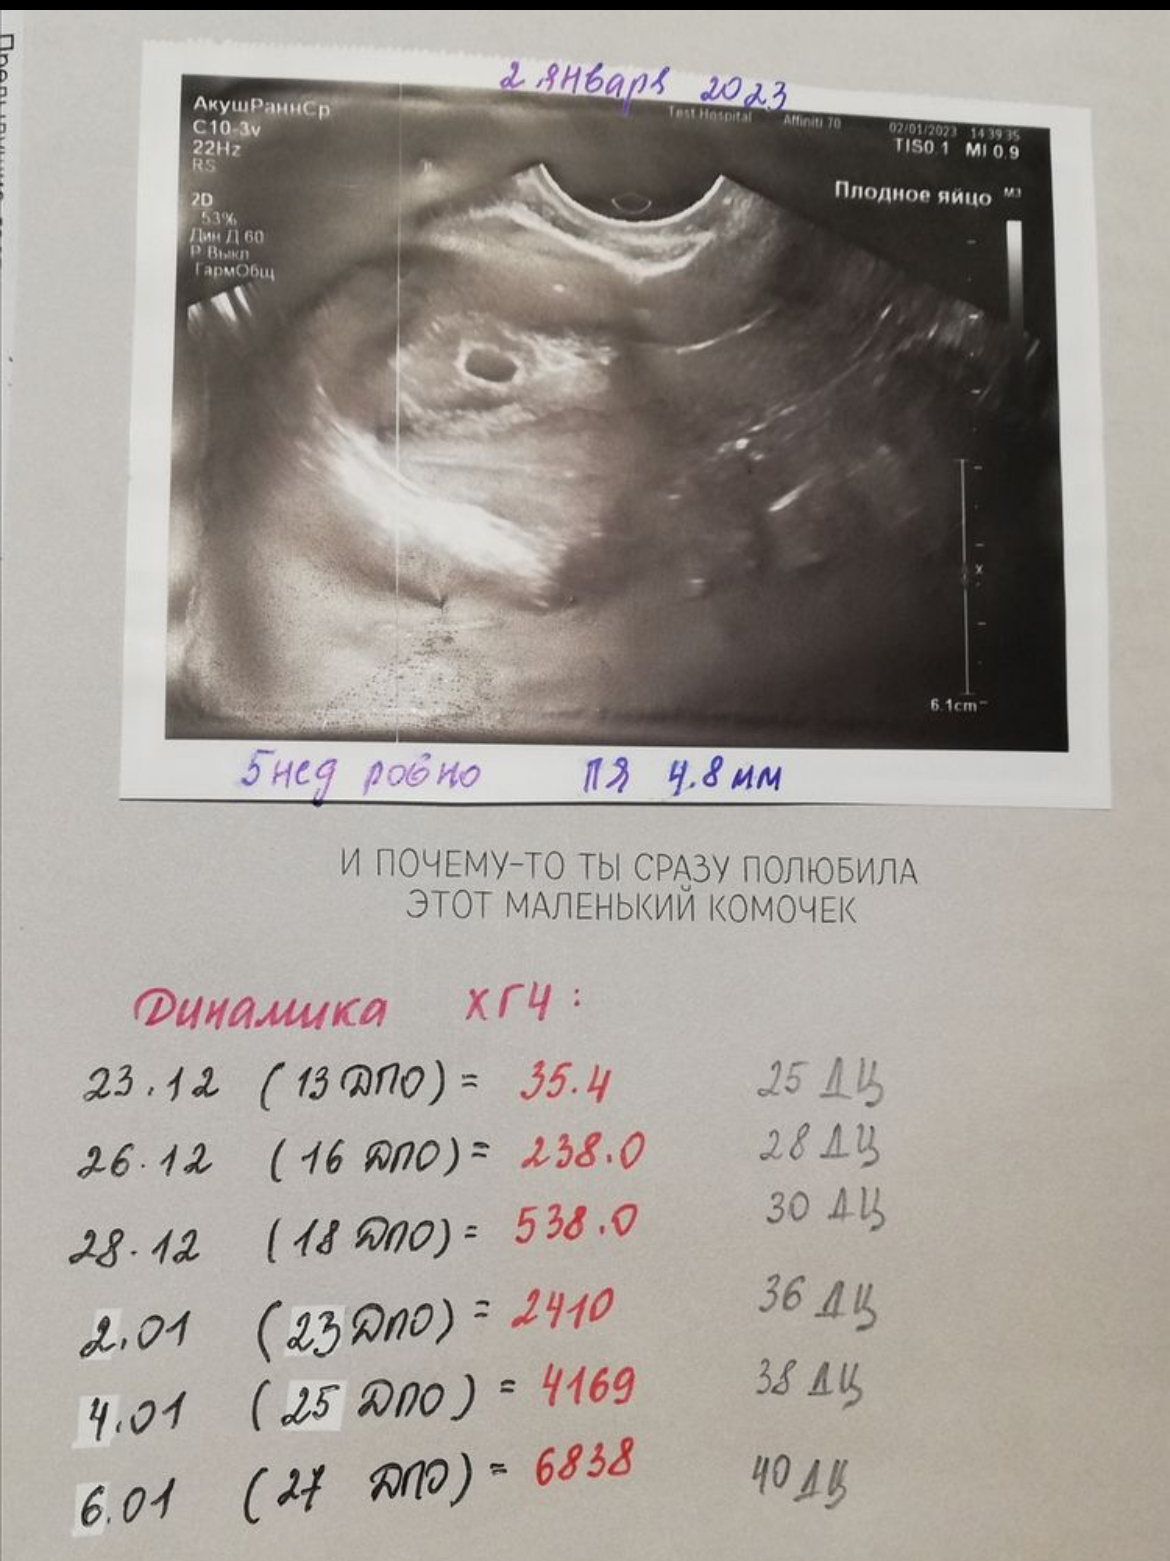

13 дпо- 35.4 был